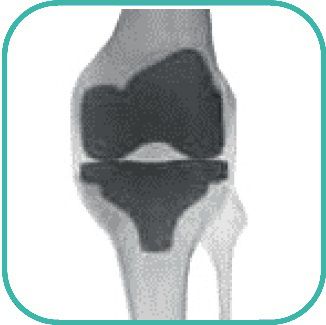

Was ist Kniegelenksarthrose / Gonarthrose?

Arthrose bedeutet starker Verschleiß eines Gelenks. An stark belasteten Stellen des Gelenks wird die Knorpelschicht immer dünner. Die Gelenkflächen gleiten nicht mehr reibungslos ineinander. Teilweie ist der Knorpel so stark abgenutzt, dass Knochenteile freiliegen. Dieser Krankheitsverlauf tritt in der Regel langsam auf.

Wie wird ein künstliches Kniegelenk implantiert?

Die Wahl der richtigen Knieendoprothesen hängt ab von

- Knochenqualität

- Stabilität der Seitenbänder

- Achsendeformität

- X- oder O-Bein

Grundsätzlich gibt es zwei Prothesentypen: Oberflächenersatz und achsgeführte Prothesen.

Oberflächenersatz

Zur Erstversorgung werden ungekoppelte Prothesen eingesetzt. So bleibt der Bandapparat des Kniegelenks weitgehend erhalten. Dieser Prothesentyp ersetzt die verschlissenen Knorpeloberflächen des Oberschenkels, des oberen Schienbeinendes und der Kniescheibenrückflächen.

Das Oberschenkelteil hat die Form einer Schale, die passgerecht auf die Oberschenkelrolle aufgesetzt wird.

Das Unterschenkelteil hat die Form einer Platte. Auf dieses Implantat wird ein Einsatz aus einem abriebfesten Kuntstoff gesetzt.

Falls eine Arthrose auch an der Kniescheibenrückfläche besteht, wird diese entfernt und durch eine Kunststoffscheibe ersetzt.

Die Prothesenanteile werden mit dem so genannten Knochenzement auf den Knochen aufgeklebt.

Achsgeführte Prothesen

In besonders schwierigen Fällen des Kniegelenks (starke Achsfehlstellung, instabiler Kapsel-Bandapparat) werden zur Erstversorgung so genannte achsgeführte Knieprothesen verwendet. Auch bei Wechseloperationen kommen sie zur Anwendung.